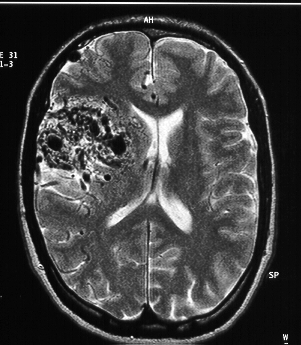

7.2 Real data

7.2.1 Auditory evoked responses

The left-ear auditory pure-tone stimulus data set from the MNE software [26, 27] was first investigated. It uses a realistic BEM (Boundary element method) head model containing dipoles located on the cortex with orientations that are normal to the brain surface. The data was sampled with MEG sensors at Hz, low-pass filtered at Hz and downsampled to Hz. One channel that had technical artifacts was ignored. The measurements corresponding to ms of data preceding each stimulus were considered to estimate the noise covariance matrix that was used to whiten the measurements. Fifty-one epochs were averaged to calculate . The activity of the source dipoles was estimated jointly with the skull conductivity for the period lasting ms after the stimulus. From a clinical perspective it is expected to find the brain activity primarily focused on the auditory cortices that are located close to the ears in both hemispheres of the brain.

The proposed method was compared with (1) a default- model that uses , which is the value corresponding to a ratio of between the scalp and skull conductivities). It is the default value used by the MNE software, and (2) the mixed norm regularization introduced in [22] also using an operator with .

We can see in Fig. 7.12 that out of the three models, the solution found by our method is the one that best agrees with the clinically expected solution of finding the activity focused on the auditory cortices whereas the other two spread the activity over several dipoles around the area. In addition, the MMSE estimator of the skull conductivity is , corresponding to a ratio of between the scalp and skull conductivities. This shows that this ratio is considerably lower than the value of typically used in earlier research [12], in agreement with recent studies [23, 13].

The estimated waveforms are presented in Fig. 7.11: all methods estimate very similar waveforms. However, the proposed method concentrates the activity of several dipoles in the same one. The different waveforms detected by our algorithm are presented separately in Fig. 7.13 where the mean value for each activation and the confidence intervals for 2 standard deviations are displayed. We can see that the two dipoles located in the auditory cortices have most of their activity concentrated in strong peaks located around ms after the stimulus, as it is clinically expected. The histograms of the sampled variables are shown in Fig. 7.14.

In summary, the proposed method is able to concentrate the brain activity more strongly in the auditory cortices (where it is expected to be) than the other two and estimates a value of that is more compatible with the findings of recent studies than the default value used by the MNE software.